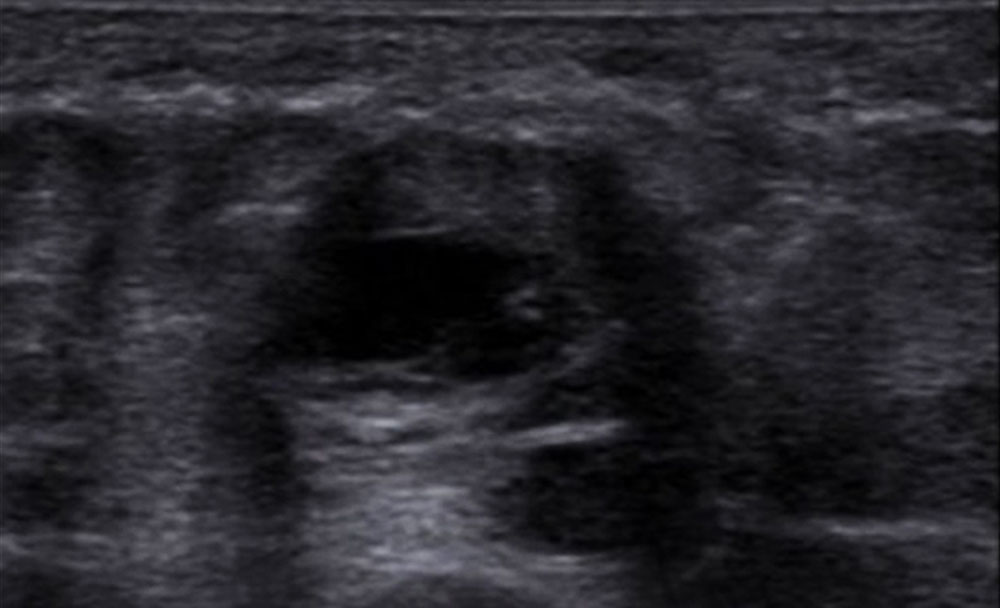

The most important imaging to detect or exclude phlebothrombosis is sonography. The affected vein section shows the thrombus contained in the vessel lumen, which cannot be compressed by compressing the vein with the transducer. Depending on age, this vascular thrombus tends to have a relatively low echogenicity initially in acute cases. The vein diameter is significantly increased by the intraluminal thrombus in the acute phase. In color-coded duplex sonography (CCDS), no color signal is found in the vein owing to the lack of blood flow, even at very low PRF settings (low pulse repetition frequency PRF = high detection sensitivity for flowing blood). With increasing thrombus age, the thrombus shrinks in size and becomes increasingly echogenic. In the further course, at least partial recanalization of the thrombosed vein occurs in favorable cases. Often beginning at the vein wall, blood (echo-free on ultrasound) again flows through the vessel surrounding the thrombus.